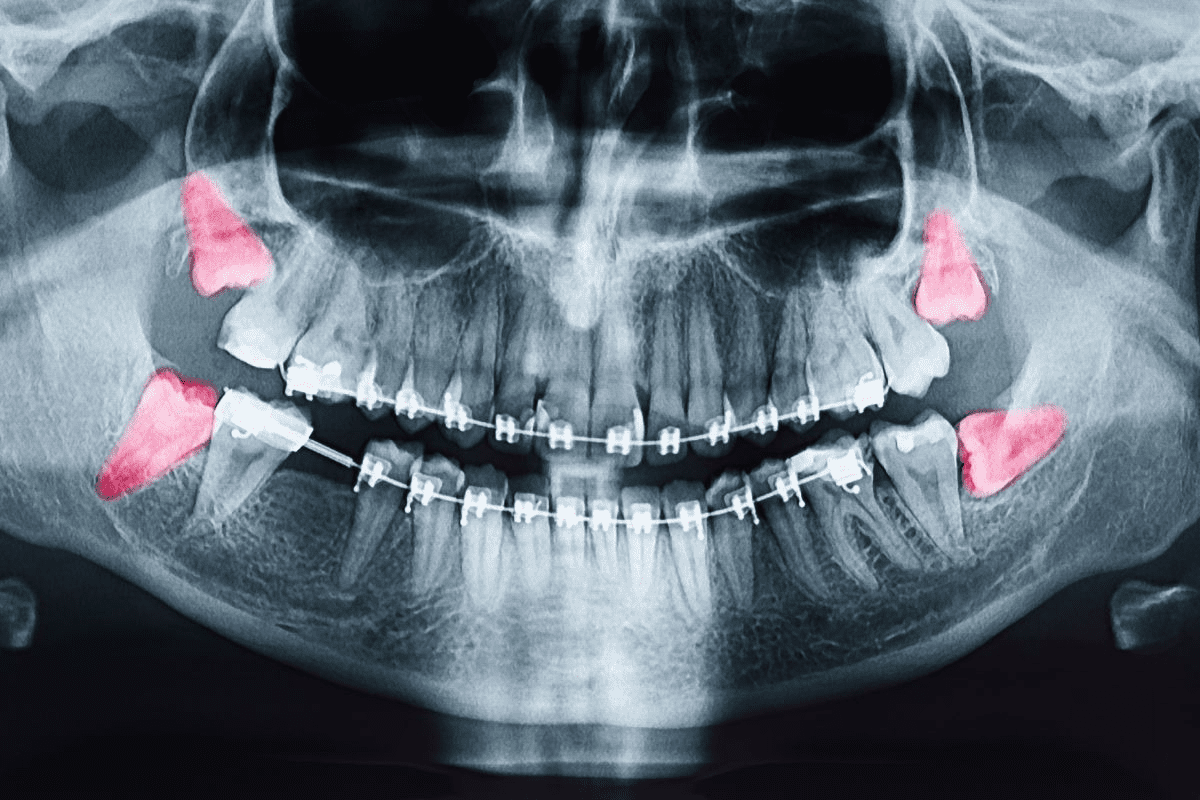

Odontogenic keratocysts are jaw cysts linked to tooth roots. They might not cause symptoms but can make the jaw bigger and could lead to breaks if not treated. Finding them early with X-rays is very important.

Imaging Methods

Imaging is very important for jaw tumor diagnosis. It gives us detailed info about the tumor’s size, location, and how far it has spread. We use:

- X-rays: Good for the first look, showing bone involvement.

- CT scans: Give detailed images of the tumor and its surroundings.

- MRI scans: Show soft tissue details, helping with tumor spread assessment.

- PET scans: Help find tumor activity, useful for cancer detection.